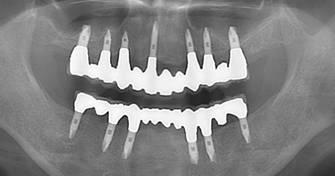

治療後。歯周病で失われた骨が回復しています。使用インプラントはスプラインツイストです。

上部構造装着後6年。ハイブリッドレジンを使用したため、少し艶がなくなってきました。上部構造の材料には金属、ハイブリッドレジン、セラミックなどがあります。セラミックはきれいですが欠けやすいため、最近はフルジルコニアを使っています。

インプラント装着後6年。順調に経過しています。12か月毎のメインテナンスをしています。